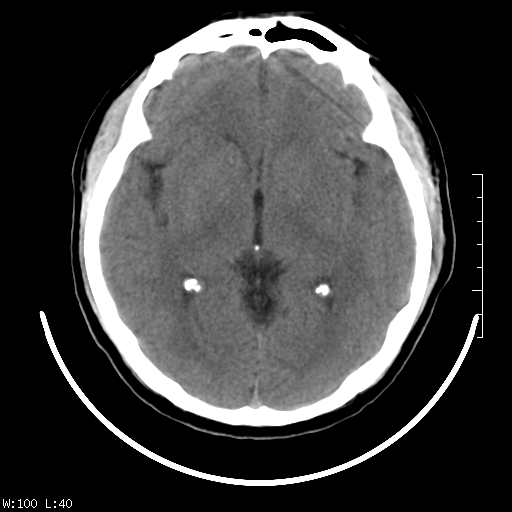

标题: CT22236:男,45,经常头痛。看看脑干正常吗? [打印本页]

标题: CT22236:男,45,经常头痛。看看脑干正常吗?

未见明显异常,建议ct增强或mri检查。

没见异常密度及形态改变啊,我认为是正常的。

颅脑ct轴位平扫颅内未见明确异常。

颅脑ct平扫未见明确异常,必要时mri检查。